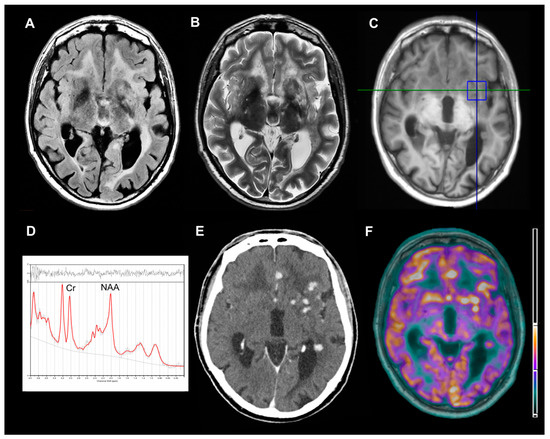

A 52-year-old man presented to our hospital with a 10-year history of focal seizures, progressive cognitive decline and motor impairment. A written informed consent was obtained from the patient. Neurological examination revealed ataxic gait, bilateral telekinetic and postural tremor, brisk reflexes, left extensor plantar response and hypoesthesia to the right side of body. Cranial and peripheral nerves were intact, and no systemic manifestations were detectable. Laboratory results were not suggestive of any inflammatory or infectious disease. Cerebrospinal fluid (CSF) analysis indicated high levels of proteins and presence of oligoclonal bands. Chest imaging, including a high-resolution computed tomography (HRCT), resulted completely normal during previous years. Brain 3T-magnetic resonance imaging (MRI) showed a leukoencephalopathy with multifocal nodular lesions hyperintense on T2/fluid attenuated inversion recovery (FLAIR) weighted images involving basal ganglia, periventricular and deep white matter (Figure 1A,B). To better understand the nature of these nodules, single-voxel 1H-magnetic resonance spectroscopy (1H-MRS), contrast enhanced computed tomography (CT) scan and fluorine-18-fluorodeoxyglucose-positron emission tomography (18F-FDG-PET)/3T-MRI were performed. The parenchymal multifocal lesions exhibited slight N-acetyl-aspartate/creatine reduction without abnormal peaks on 1H-MRS (Figure 1C,D), enhancement after the administration of contrast agent (iopromide) on CT (Figure 1E) and hypermetabolism on 18F-FDG-PET/3T-MRI (Figure 1F). Furthermore, no leptomeningeal enhancement was detected. All these findings excluded primary neoplasms, metastasis, neurotuberculosis, neurocysticercosis and brain abscess, strongly suggesting a diagnosis of neurosarcoidosis [2]. Therefore, a whole-body 18F-FDG-PET/CT was performed in order to identify subclinical extraneural sarcoidosis localizations [1]. Then, a hypermetabolic peribronchovascular nodule of the left lung upper lobe was found (Figure 2A). Whole-body 18F-FDG-PET/CT was performed 65 minutes after the injection of 370 MBq of 18F-FDG by using three minutes/bed 2D scan. The patient was fasted for six hours. Brain 18F-FDG-PET/3T-MRI was acquired 45 minutes after 185 MBq of 18F-FDG injection. The patient was placed in a quiet room 20 minutes before injection and instructed to not to speak and read. The 10 minutes PET scan of the brain was corrected for movement by using a contemporary blood oxygenation level dependent (BOLD) sequence. Given that the patient has always refused brain sampling, pulmonary biopsy (Figure 2B,C) documented the presence of systemic sarcoidosis, supporting a diagnosis of probable neurosarcoidosis according to established diagnostic criteria [1].

Figure 1. Structural, spectroscopic and metabolic findings of the brain nodular lesions. Axial fluid attenuated inversion recovery (FLAIR)-weighted (A) and T2-weighted (B) 3T-magnetic resonance imaging (MRI) images demonstrating several parenchymal nodular lesions and leukoencephalopathy. Single-voxel 1H-magnetic resonance spectroscopy (1H-MRS) involving basal ganglia lesions (C) and relative spectrum (D) showing N-acetyl-aspartate/creatine (NAA/Cr) reduction, without abnormal lactate or lipids peaks (NAA/Cr ratio was 0.873). Axial contrast-enhanced computed tomography (CT) (E) and fluorine-18-fluorodeoxyglucose-positron emission tomography (18F-FDG-PET)/3T-MRI (F) images demonstrating iopromide enhancement and hypermetabolism of all nodular lesions (the units are representative of percentage of overlap between MRI and PET).

Sarcoidosis of CNS without systemic manifestation can be present in approximately 10% to 19% of patients with neurosarcoidosis [1]. This condition might manifest as multiple or solitary nodules, periventricular white matter lesions, cranial nerves and meningeal thickening with contrast enhancement, hydrocephalus, involvement of hypothalamic–pituitary axis or long-extending myelitis. Brain parenchymal lesions may be seen in about 20% of cases [1]. MRI is the study of choice to evaluate CNS involvement but although has high sensitivity (82%–97%) it lacks in specificity [1]. Indeed, differentiating these nodular lesions from neoplastic (such as primary neoplasms and metastasis), or infective disorders (such as neurotuberculosis, neurocysticercosis and brain abscess), especially in absence of leptomeningeal involvement, may be challenging. For these reasons, advanced neuroimaging techniques may provide further support to the differential diagnosis. 18F-FDG-PET is very useful to identify CNS and extraneural localization of sarcoidosis [1] showing an increased metabolic uptake, despite discrepancy between MRI and FDG-PET findings that have been previously reported in cases of spinal and brain sarcoidosis [3,4,5]. In our case, no MRI and FDG-PET imaging discordance was found, and the hypermetabolic pattern of the multifocal brain lesions allowed us to exclude a diagnosis of neurocysticercosis and neurotuberculosis [2,6], in which lesions typically show a decreased metabolic uptake. However, an increased metabolic uptake may be detected not only in the neurosarcoidosis but also in metastasis, primary neoplasms and brain abscess. 1H-MRS allowed us to exclude these alternative diagnoses, because it showed a non-specific pattern of slight N-acetyl-aspartate/creatine reduction without abnormal peaks. Indeed, metastasis and primary neoplasms display suppressed N-acetyl-aspartate and creatine with elevated choline and lactate; whereas brain abscess are typically associated to abnormal peaks of lactate, lipids, amino acids, acetate and succinate [2,7].